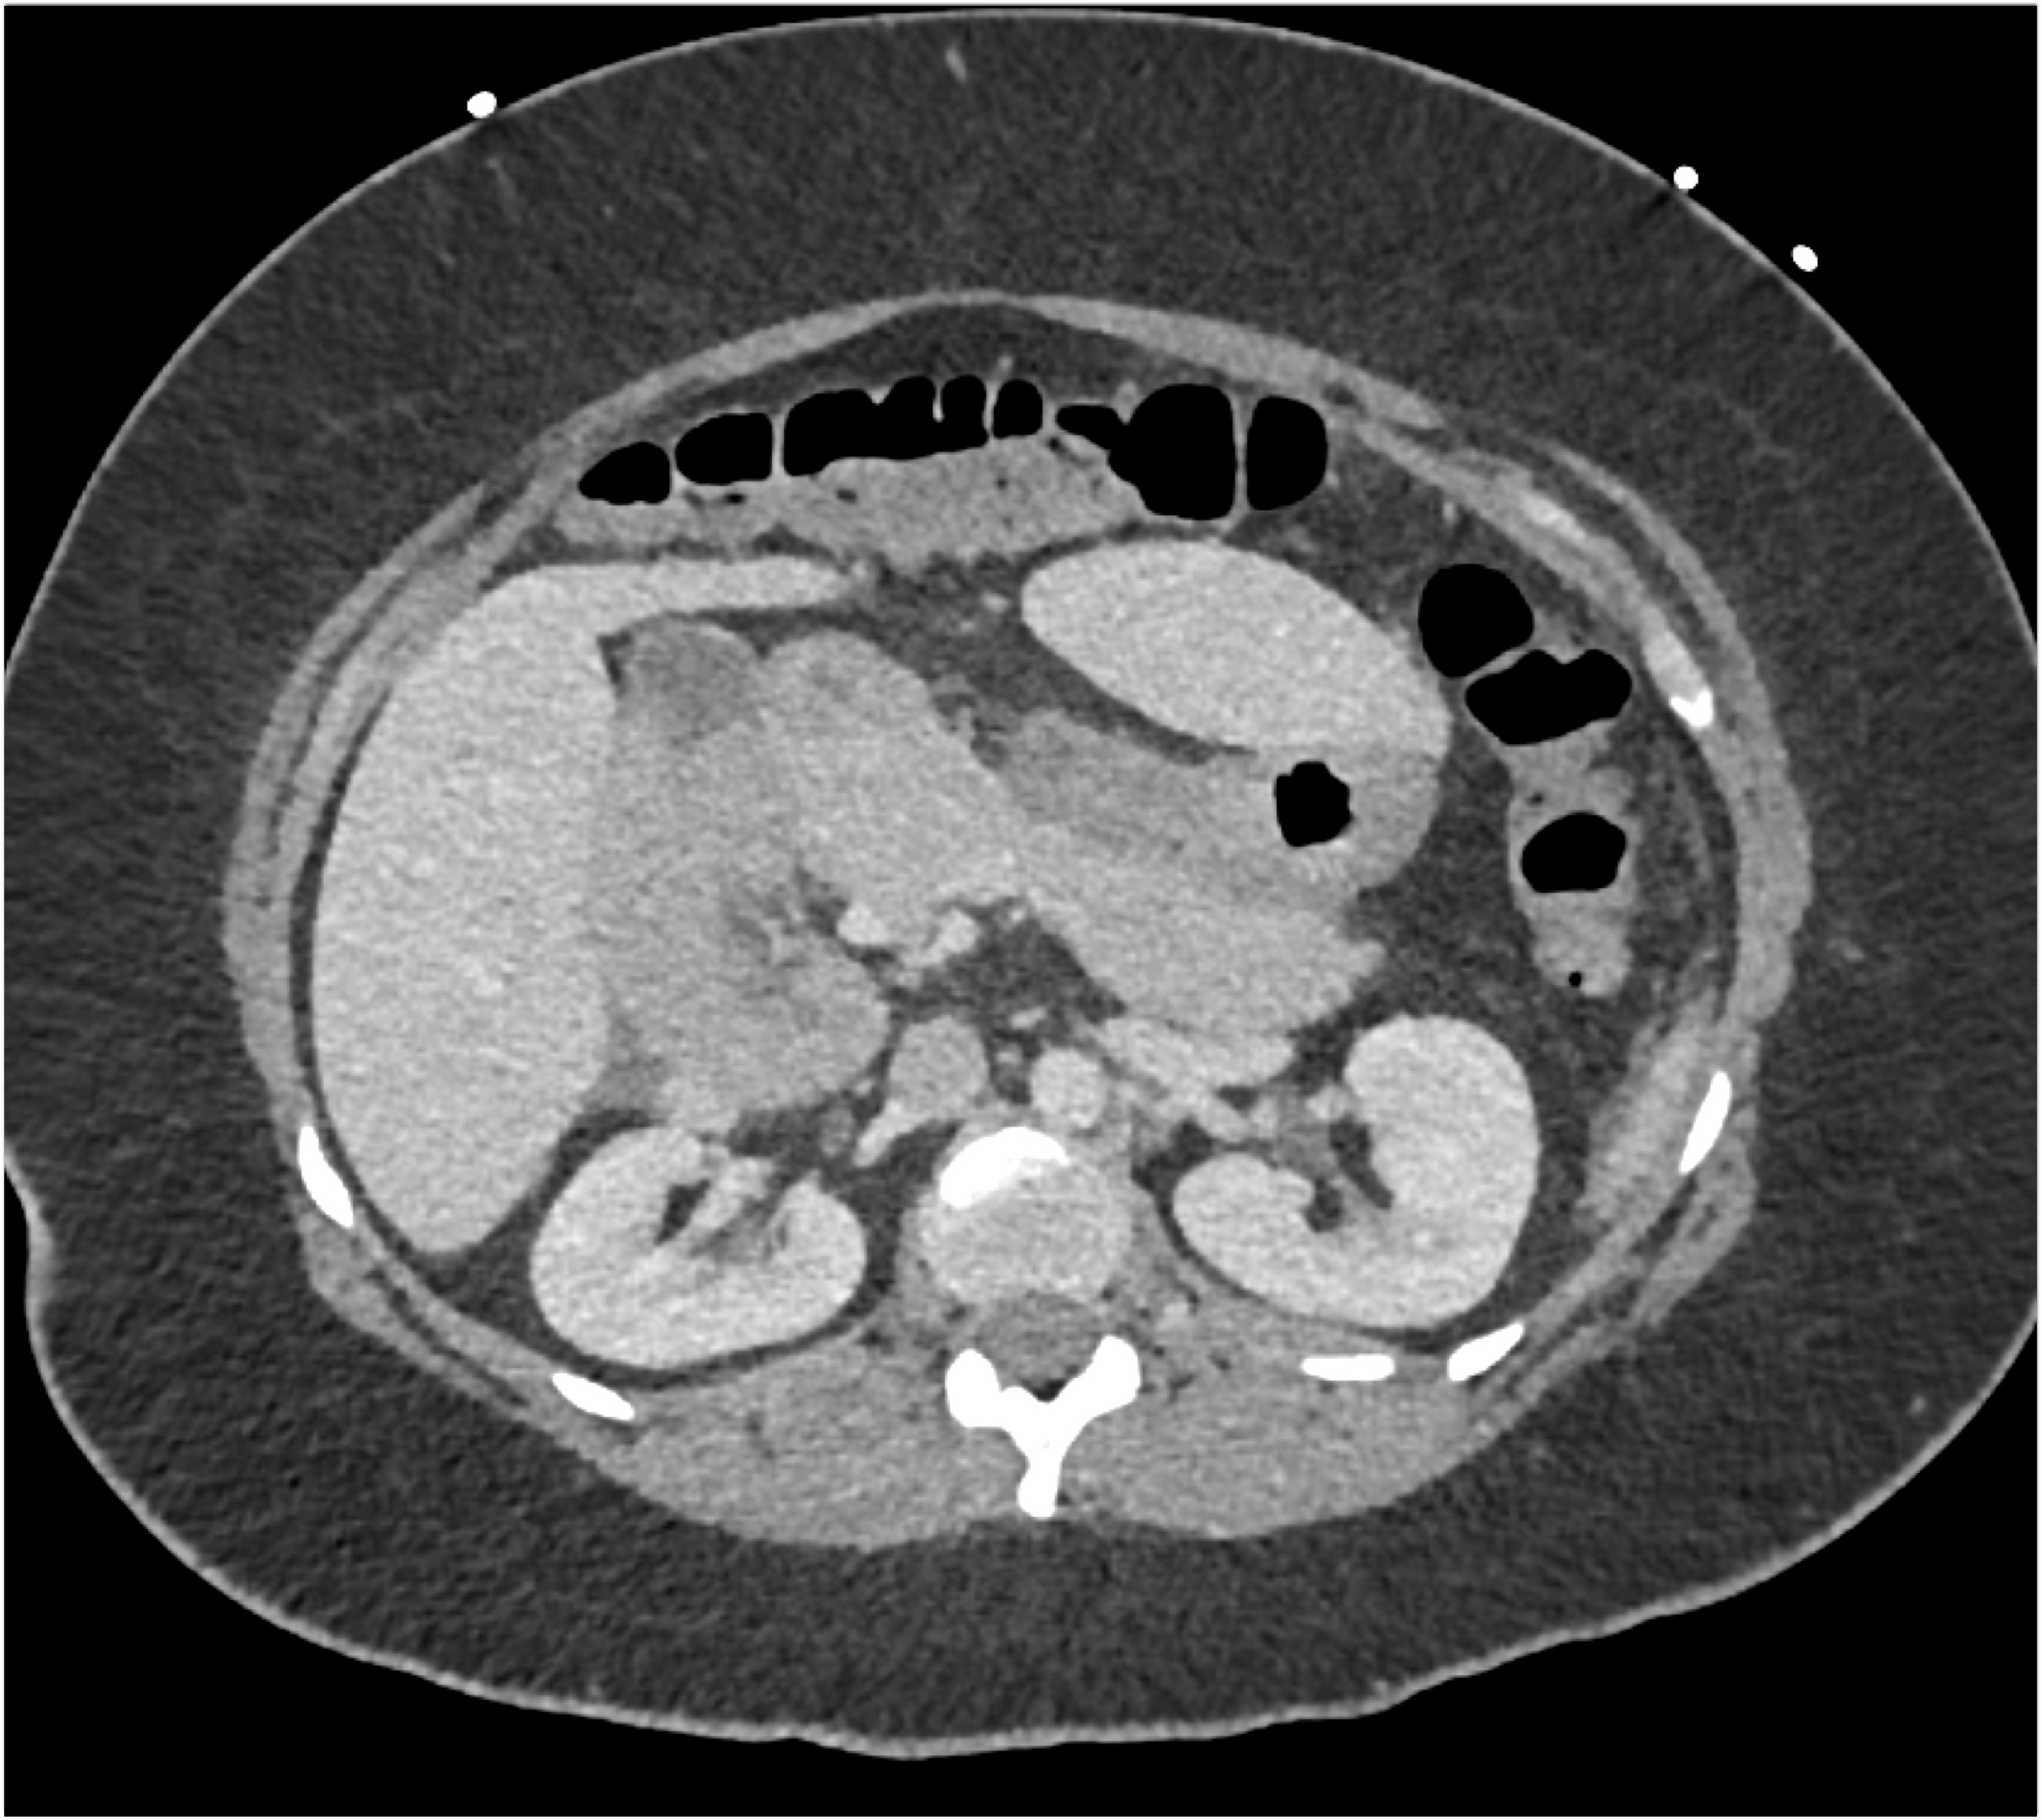

- Evaluate the CT images of each question carefully.